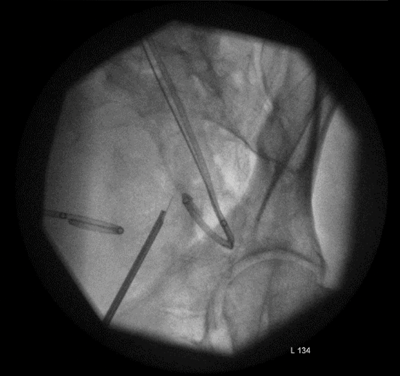

Figure 2.

The lower ureter was tortuous and of the ‘fish-hook’ type. A nephrostogram revealed a stricture at the vesicoureteric junction (VUJ) and incision of the VUJ using a Collins knife failed to demonstrate the lumen (Figure 2 and 3).